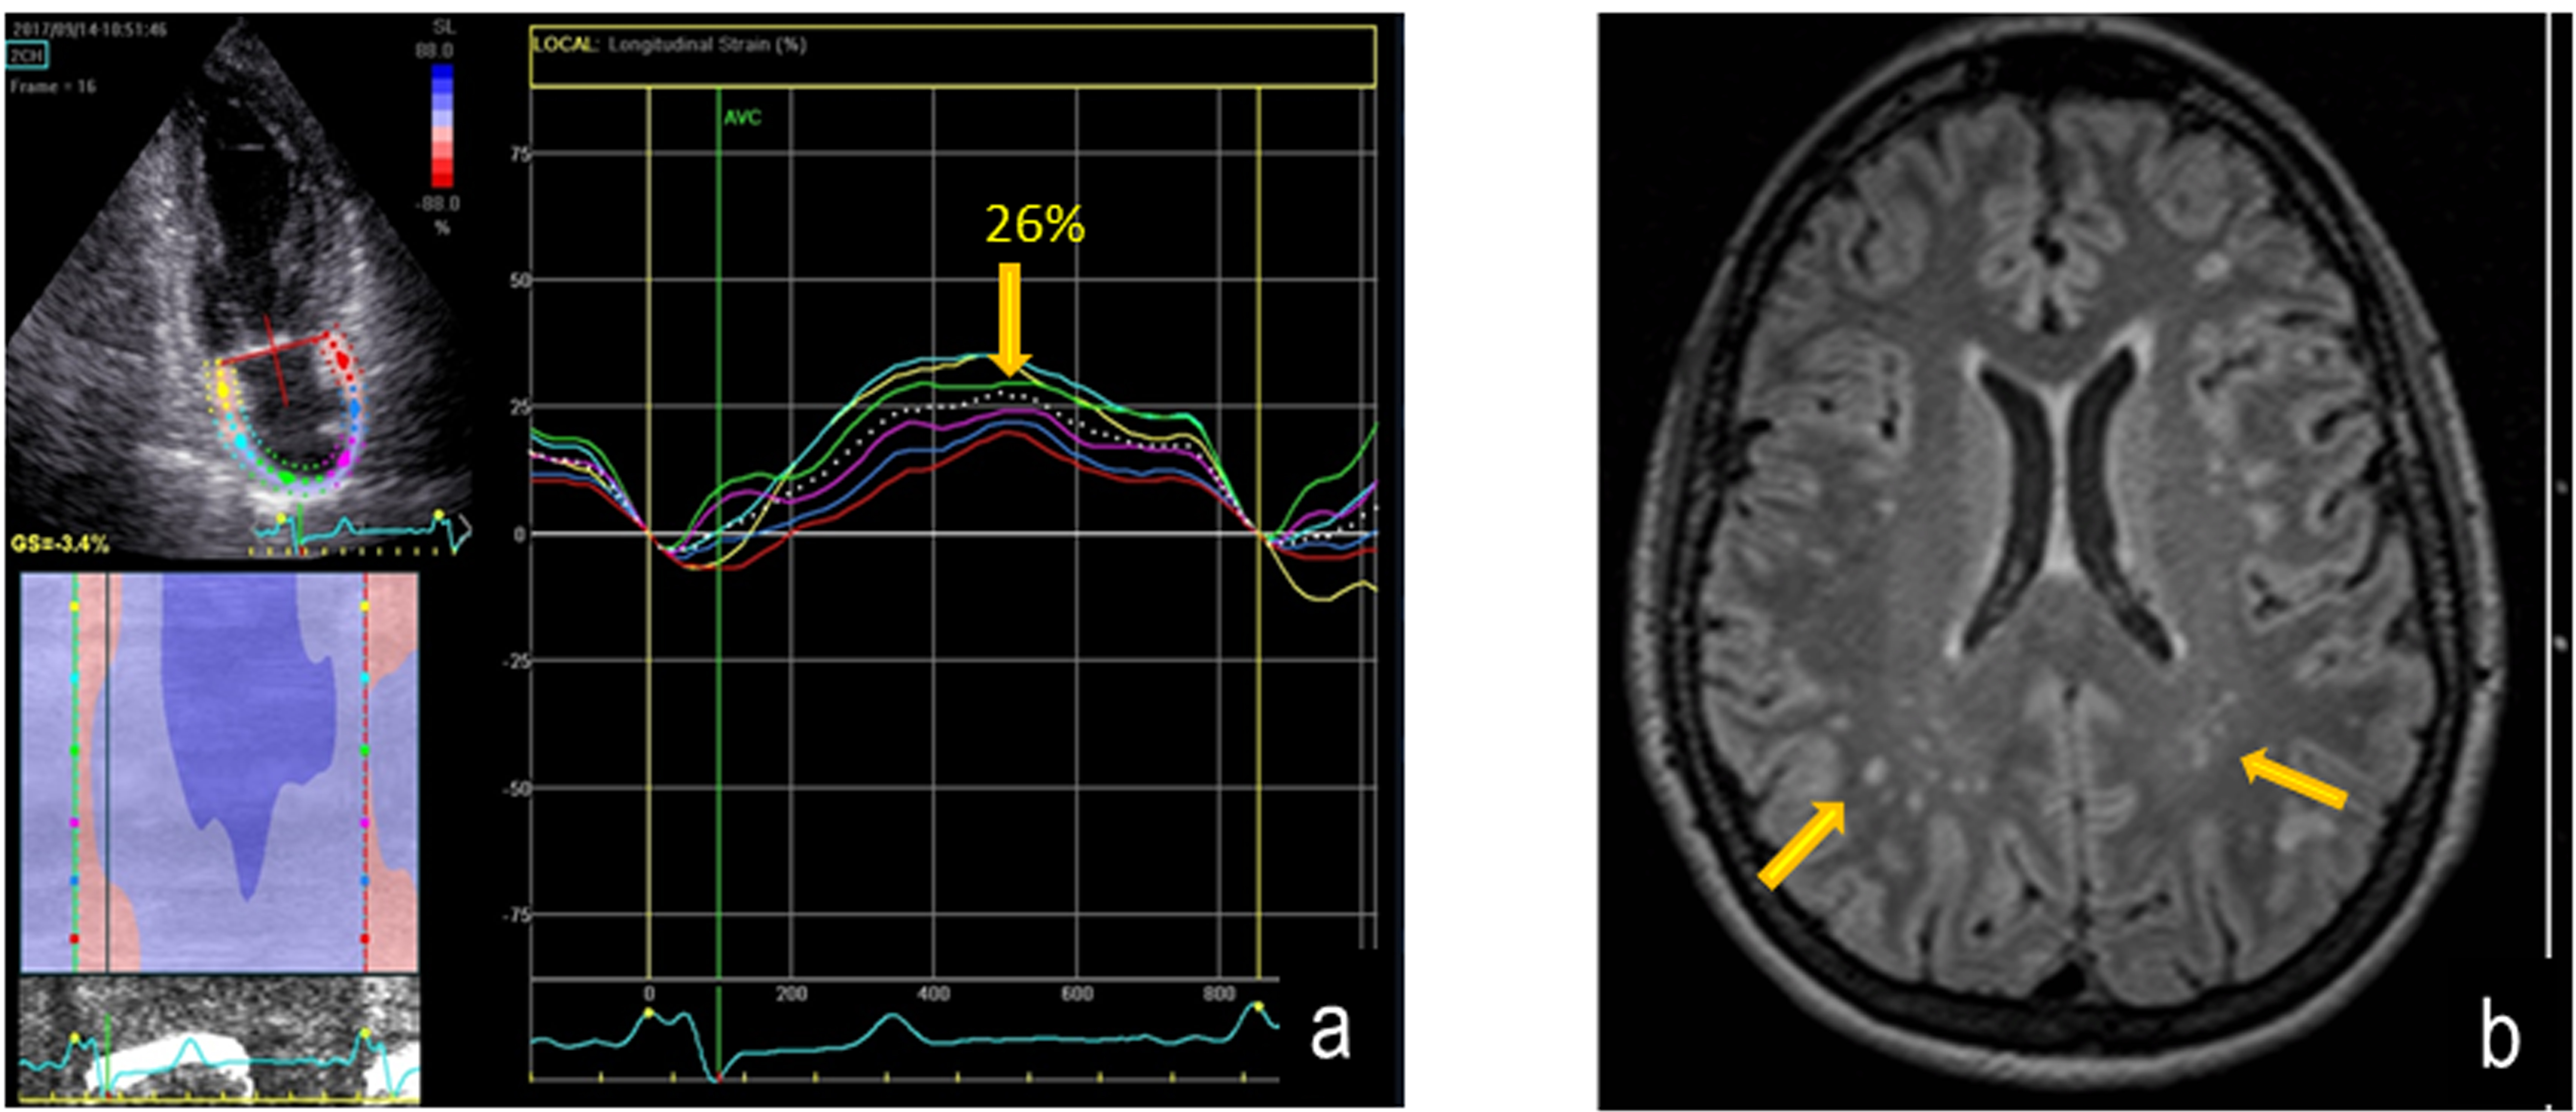

An example of AFD patient with white matter involvement on axial FLAIR MRI and reduced PALS is shown in Figure 3. By dividing AFD patients according to FS (<1 normal, ≥1 abnormal), the 13 patients with FS≥1 showed a lower PALS (p=0.0003) in comparison with FS<1, without significant difference of LA volume index (Table 3). The other echocardiographic measurements, including LVMi and GLS, did not differ significantly between the two subgroups (data not in Table):

Figure 3: Reduction of PALS (left panel) and parallel axial FLAIR MRI image showing multiple white matter hyper intensities lesions (arrows) in a AFD patient. Fazekas score is = 1.